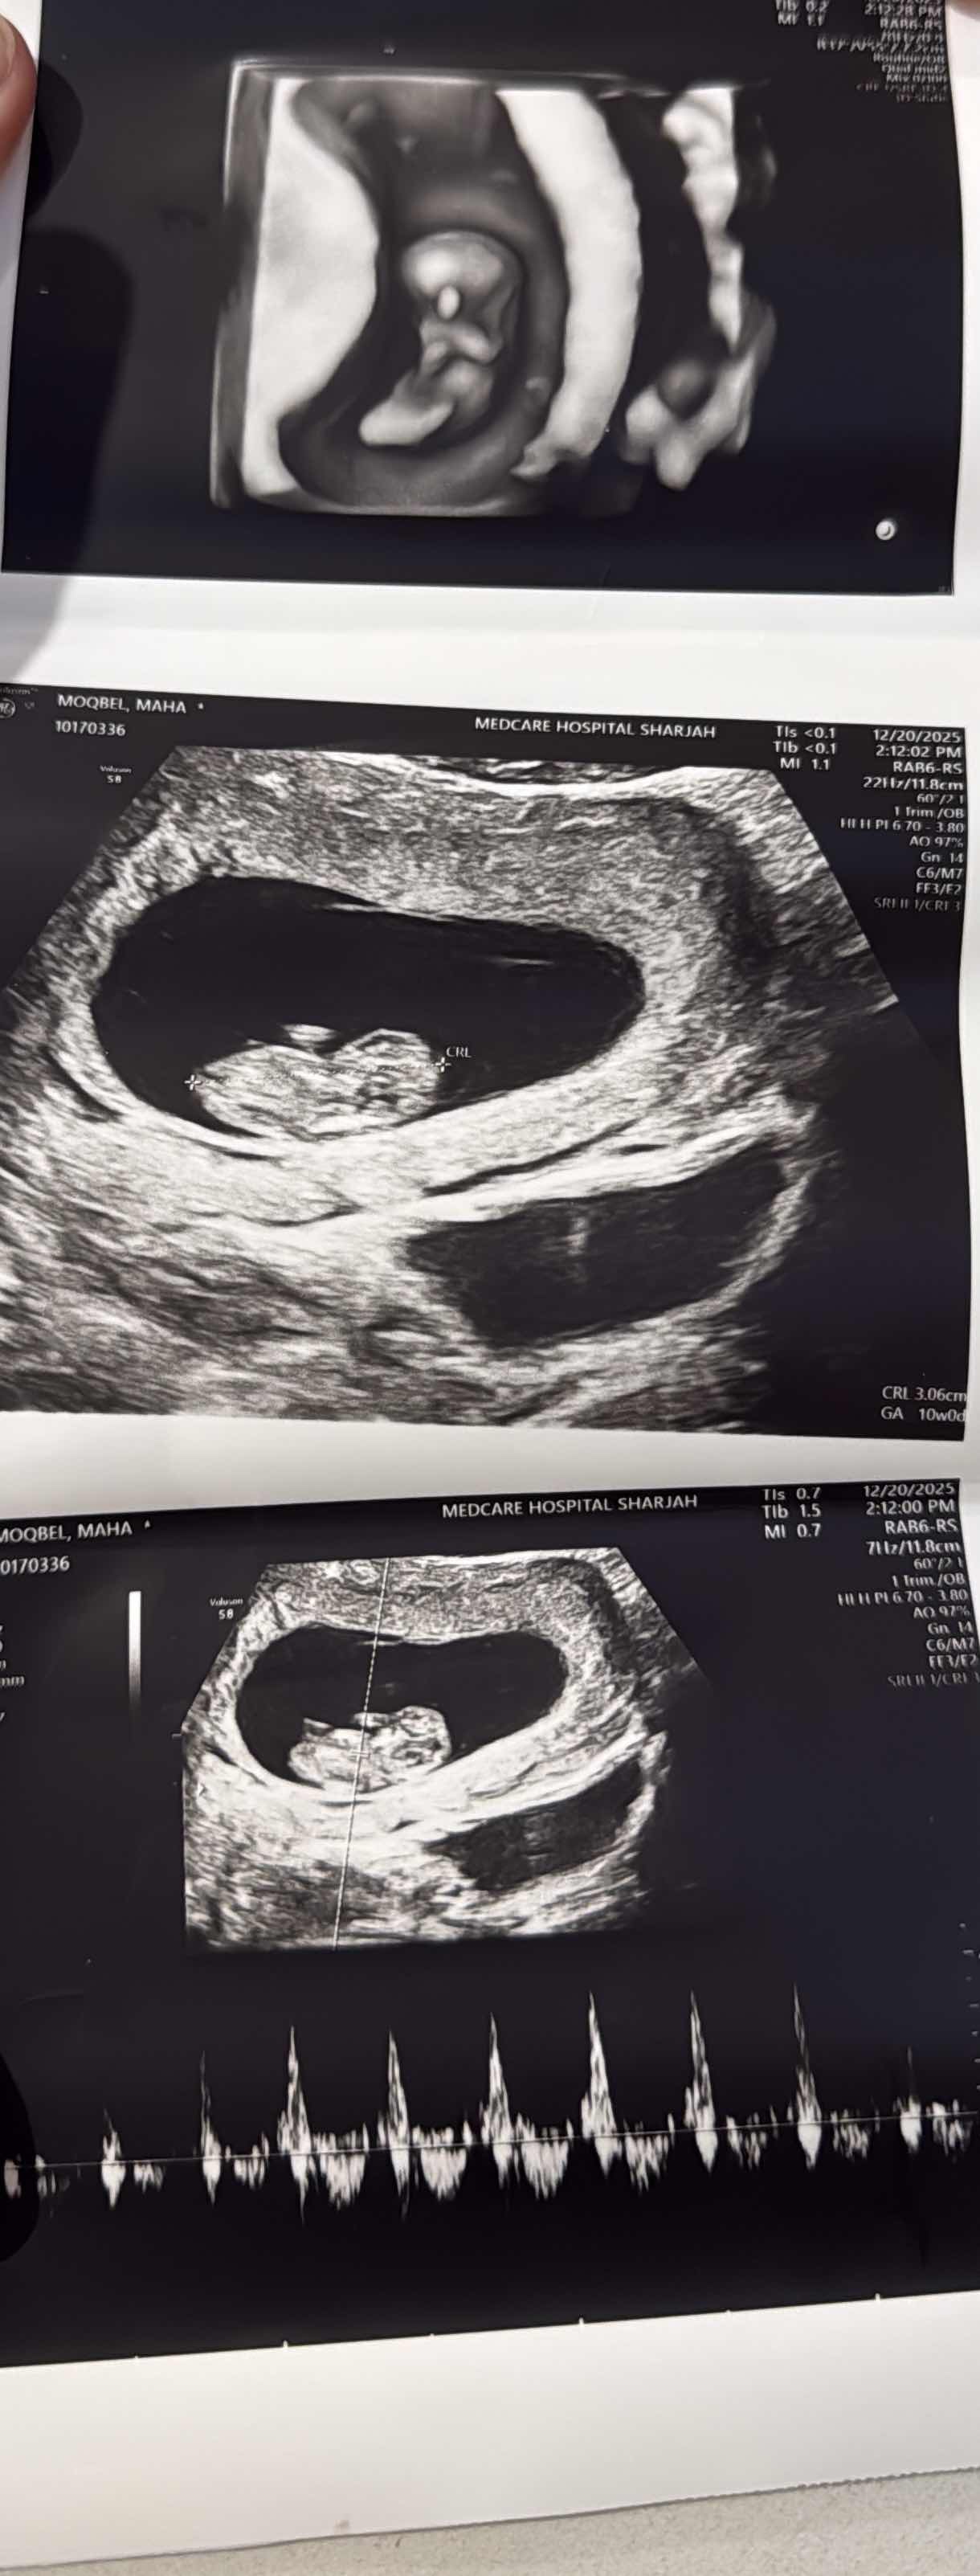

عمر الحمل طبيعي ام لا

هذا طبيعي..لأننا نحسب بالأسابيع من بداية آخر دورة وليس من الحمل الفعلي والأسابيع حسبتها تختلف عن الأشهر